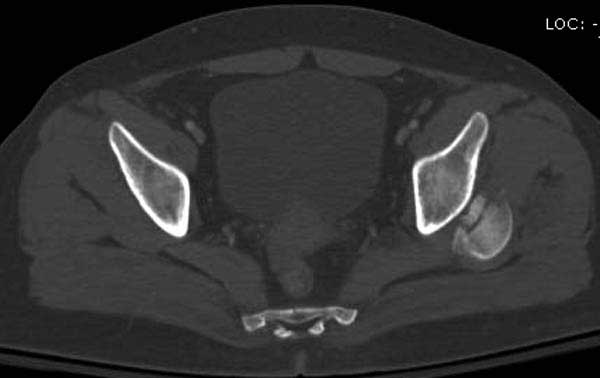

Женщина 28 лет, политравма.

По протоколу обследования больных с травмой сделаны все исследования и выставлен диагноз: разрыв печени и селезенки; множественные переломы ребер и лицевого черепа; стабильный перелом позвоночника, переломо-вывих головки левого бедра, перелом диафиза правого бедра, переломо-вывих правого тарана.